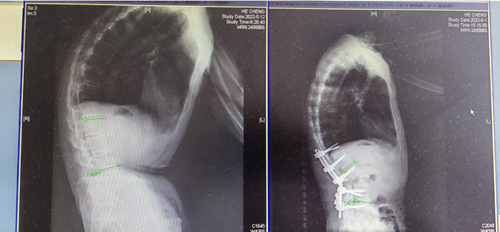

入院后,该院脊柱外科主任、主任医师罗为民教授带领团队对刘梁进行了详细的查体,发现刘梁强制性脊柱炎后凸畸形病程较长,畸形角度较大,并且畸形对心脏和胸廓造成了一定的压迫,严重影响了刘梁的心肺功能,矫形手术必须尽早实施。针对刘梁强直性脊柱炎造成严重后凸畸形的情况,罗为民主任结合术前影像学检查制定了个性化矫正方案和周密的术前规划,并最终确定了经腰3椎体PSO(经椎弓根椎体截骨矫形)的手术方式。

8月5日,刘梁被送入手术室,5个小时后,矫正手术顺利结束,刘梁家人悬着的一颗心算是落了下来。术后,刘梁的身体外观较术前得到了明显的改善,没有出现任何手术并发症。术后3天下地行走时,刘梁能挺直腰板,目视前方,身高也从154cm增至169cm。终于可以抬头挺胸,不用担心开车影响视线和安全;终于可以平卧,睡个好觉了!刘梁及家人紧握着罗为民主任的手,感激和喜悦之情溢于言表。